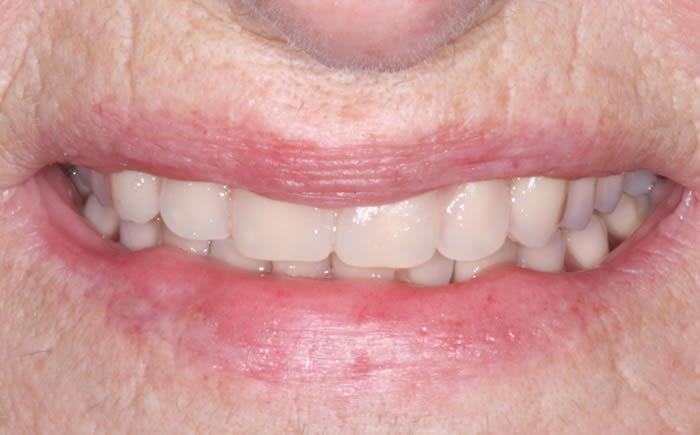

Full arches of teeth replaced by dental implants

Case One (5 images)

Full set of lower teeth fixed onto five dental implants.

Case Two (8 images)